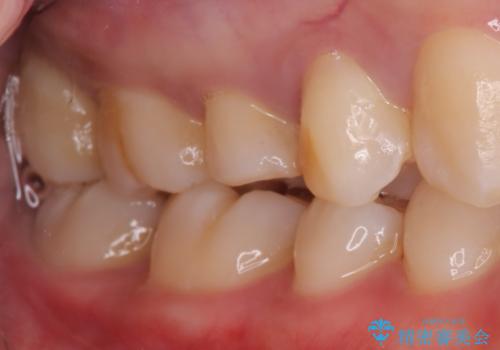

- 主訴:他院で根っこの治療を行っていたところ、根が細く治療が難しいと言われてしまった

右上5番目の歯が根管治療途中となっており、前医院にて根管が狭く治療が難しいと言われてしまいセカンドオピニオンで当院にいらっしゃいました。

右上5番レントゲン写真上では根管が確認しずらく、根管の狭窄が予想されました。マイクロスコープを使用し、根尖部まで器具を到達させ十分根管洗浄を行うことができました。